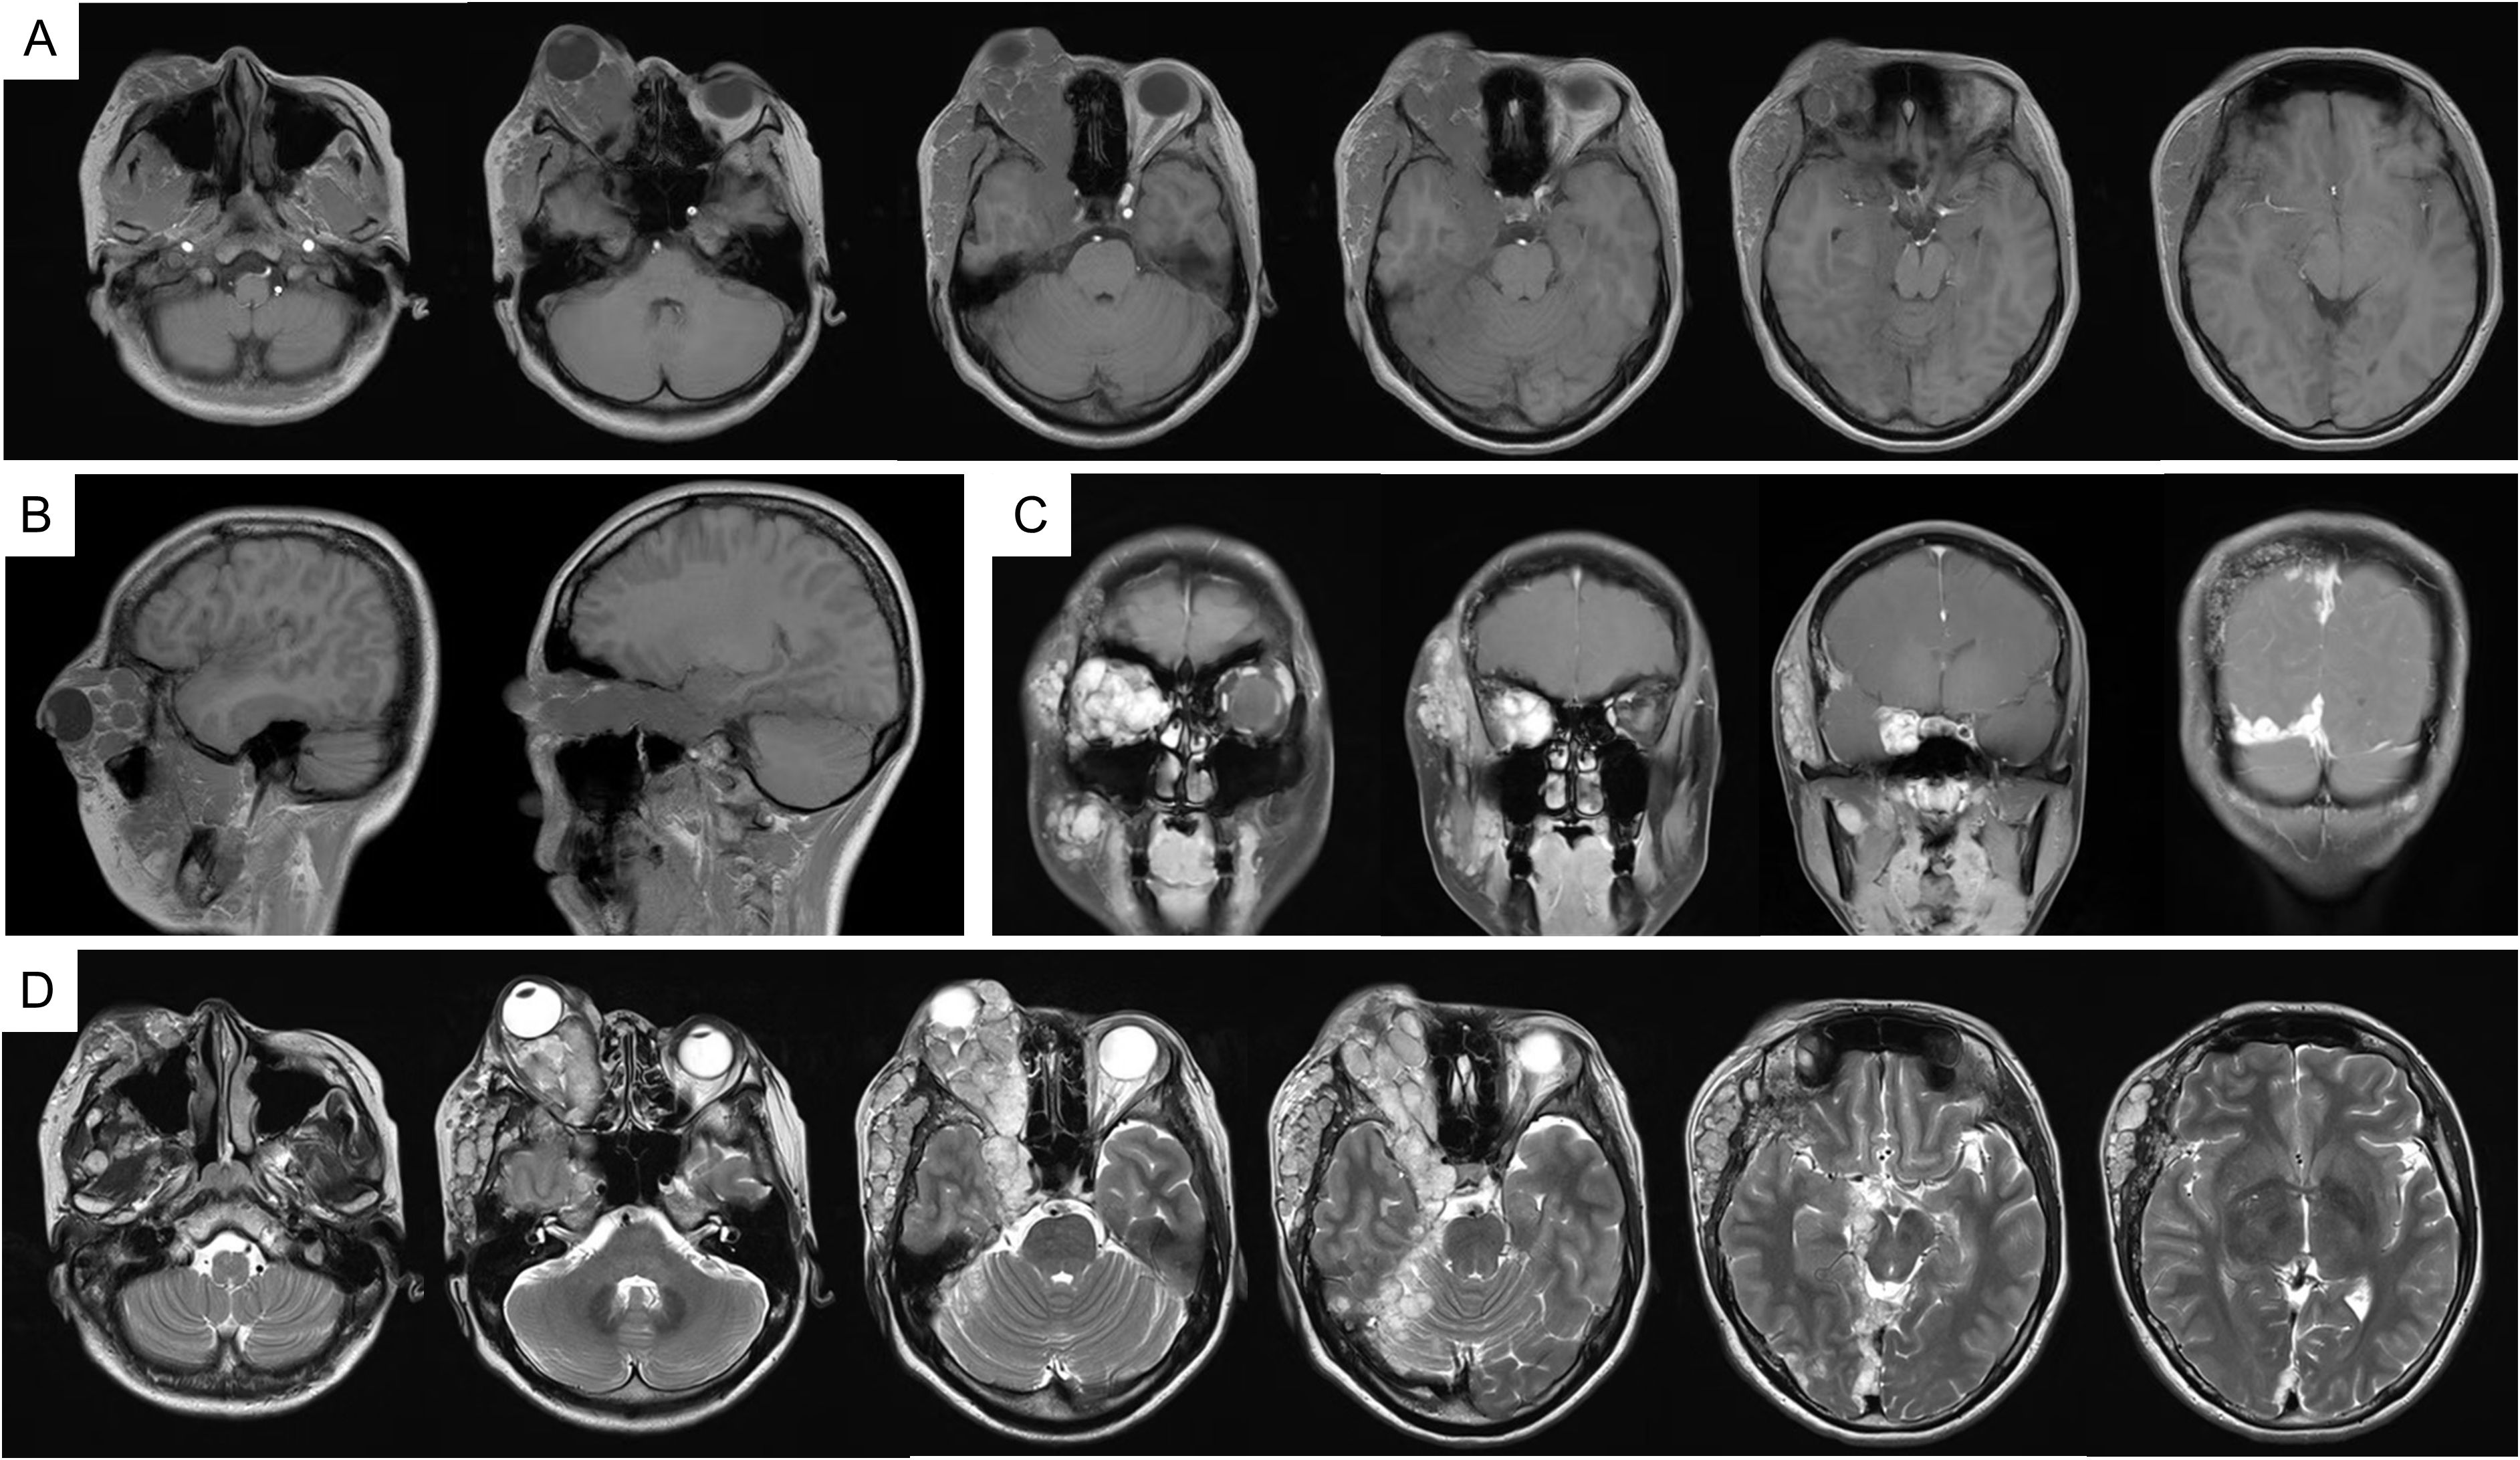

In fact, the patient tolerated the radiotherapy well and experienced no significant adverse effects during treatment. At two months post-radiotherapy, marked improvement in right facial swelling was observed. MRI confirmed a reduction in both subcutaneous soft tissue swelling and cerebral hemisphere edema (Supplementary Figure 3). Follow-up evaluations were conducted every six months. At six months post-radiotherapy, imaging showed no evidence of disease progression (Supplementary Figure 4). Encouragingly, there was 69% and 79% volume reduction at six and thirteen months. The patient’s facial symmetry has been restored and there has been no evidence of tumor progression (Figure 4), signifying the effectiveness and tolerability of the treatment. Unfortunately, the patient has persistent ptosis of the right eyelid and unrestored vision due to irreparable neurological damage. Postoperative hypofractionated HA radiotherapy was administered for the patient to address the remaining tumor and prevent further progression. The clinical timeline of this patient was illustrated in Figure 5.

Figure 4

Figure 4. MRI imaging at 13 months follow up radiology. (A) T1WI; (B) T1WI-C coronal view; (C) T1WI-C sagittal view; (D) T1WI-C; (E) T2WI-TSE.